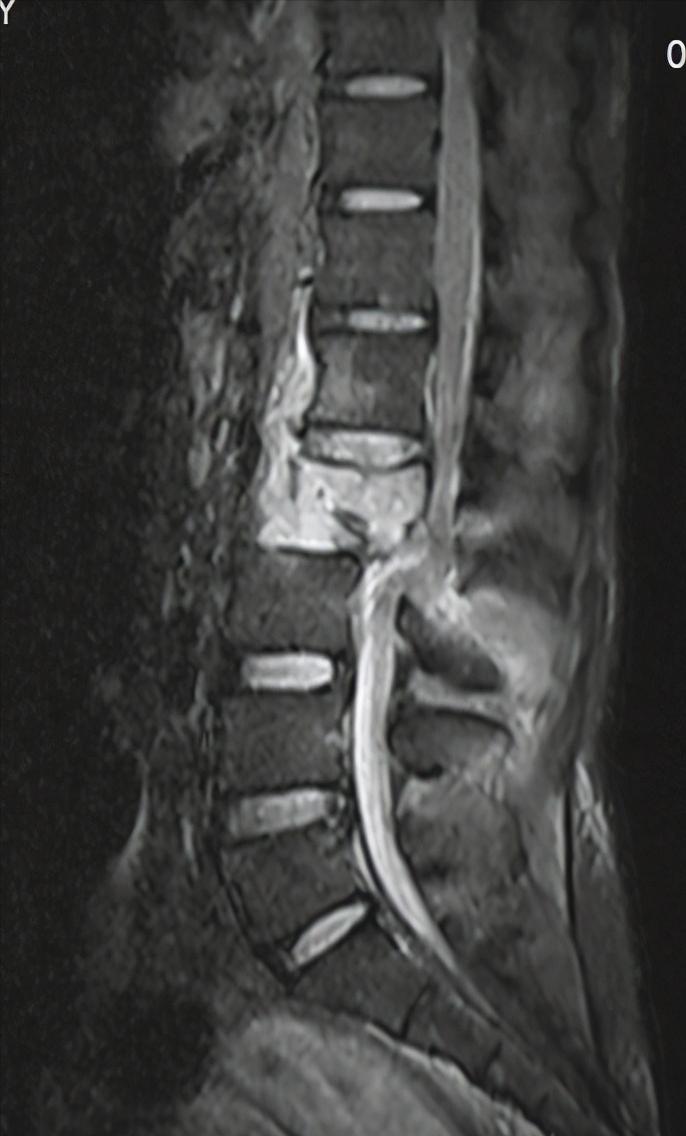

腰椎MR见脊髓明显卡压